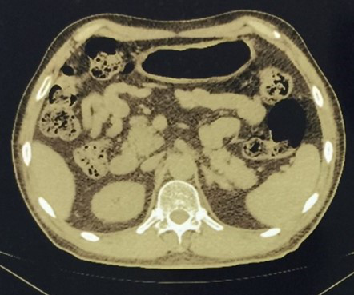

复查胸部+腹部CT(2019-04-16,本院):左侧肾上腺见结节样高密度影,大小约3.6*2.6cm,CT值31HU,较前稍增大。考虑转移。

2019-04-16:

2019-04-19:

2019-10-31胸腹部CT:左侧肾上腺见团块状软组织密度影,大小约3.6*5.2cm,CT值25HU,较前稍增大,其内可见斑片状边缘模糊低密度影。考虑转移瘤,较前增大。